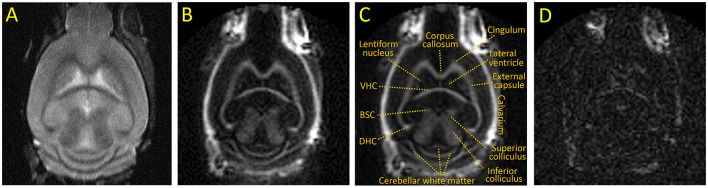

Purpose: To test the ability of inversion-recovery ultrashort echo time (IR-UTE) MRI to directly detect demyelination in mice using a standard cuprizone mouse model.

Methods: Non-aqueous myelin protons have ultrashort T2s and are "invisible" with conventional MRI sequences but can be detected with UTE sequences. The IR-UTE sequence uses an adiabatic inversion-recovery preparation to suppress the long T2 water signal so that the remaining signal is from the ultrashort T2 myelin component. In this study, eight 8-week-old C57BL/6 mice were fed cuprizone (n = 4) or control chow (n = 4) for 5 weeks and then imaged by 3D IR-UTE MRI. The differences in IR-UTE signal were compared in the major white matter tracts in the brain and correlated with the Luxol Fast Blue histochemical marker of myelin.

Results: IR-UTE signal decreased in cuprizone-treated mice in white matter known to be sensitive to demyelination in this model, such as the corpus callosum, but not in white matter known to be resistant to demyelination, such as the internal capsule. These findings correlated with histochemical staining of myelin content.

Conclusions: 3D IR-UTE MRI was sensitive to cuprizone-induced demyelination in the mouse brain, and is a promising noninvasive method for measuring brain myelin content.